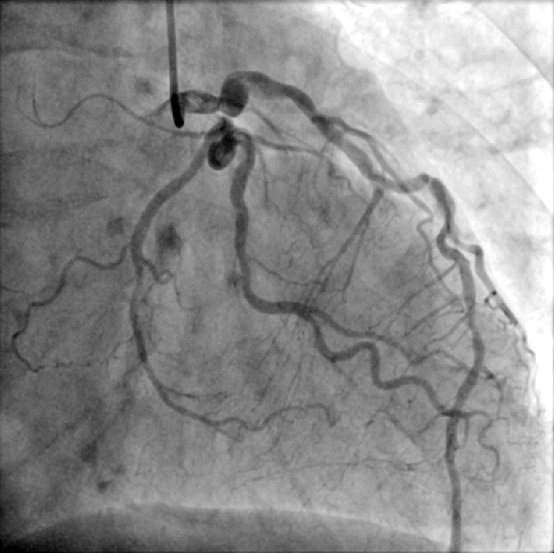

A 64-year-old male with chest pain and tightness during exertion for 2 months, relieved by rest. Past history: type 2 diabetes, hypertension. No smoking or family history. Sinus rhythm EKG. Clear lungs, no cardiomegaly on chest x-ray. Angiography: LM bifurcation (Medina 1,1,1), diffuse LAD, severe LCX AS, 95% eccentric LAD, long RCA CTO. Syntax score 25, EuroScore II 0.84%. CABG advised, patient sought second opinion here.

Cath report from referring hospital-LM:bifurcation lesions (1,1,1 type; 90%, 90%, 30% stenosis)-LAD:Diffuse lesions with acute bends-LCX:Severe AS changes with discrete 95% due to eccentric plaque at proximal LAD-RCA:Long CTO lesion